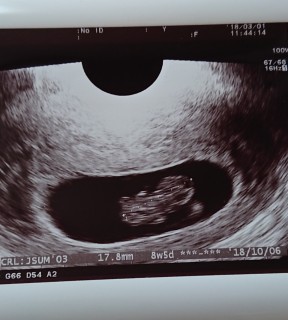

無事に成長してました(*^-^*) 17.8mmで先生も「問題なし」と言ってくれました。

初期で何かと心配な時期ということで前回から1週間後に再診。順調に1.77cmへ成長していました!心拍も問題なし。風疹大流行のため、先々の妊婦検診を待たずに風疹抗体検査をしました。